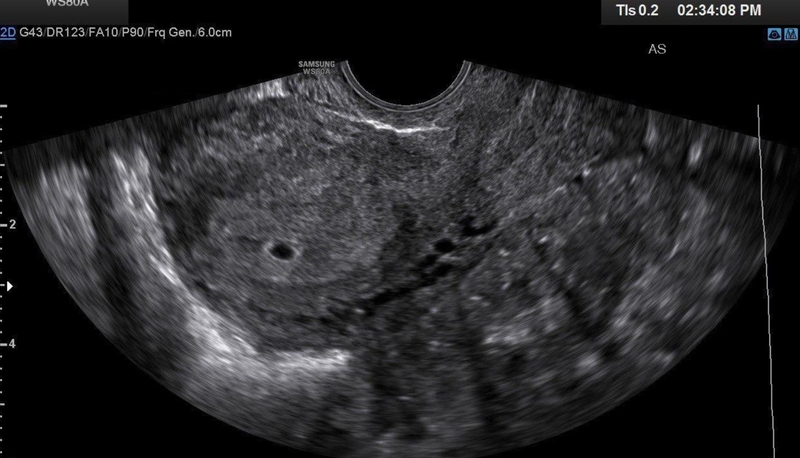

Theo chia sẻ từ bác sĩ chuyên khoa phụ sản cho biết, trên siêu âm đường bụng thường phải đến khoảng tuần thai thứ 6 – 7 mới có thể quan sát được phôi thai và những hoạt động của thai nhi. Túi thai 11mm tương đương với tuần thai thứ 5 và ở thời điểm này, khi được chẩn đoán túi thai 11mm chưa có phôi, bác sĩ thường khuyên mẹ bầu quay lại siêu âm thêm 1 – 2 tuần nữa để xác định đúng hơn trạng thái của thai nhi.

Vậy túi thai 11mm chưa có phôi thai có sao không? Túi thai 11mm chưa thấy xuất hiện phôi, mẹ bầu có thể cần phải xét nghiệm beta-hCG để hỗ trợ quá trình đánh giá cụ thể hơn tình trạng thai nhi, phôi thai xuất hiện hay chưa, nguyên nhân khiến phôi chưa xuất hiện.

Nhìn chung, túi thai 11mm chưa có phôi không thể kết luận bất cứ điều gì vì phôi có thể xuất hiện chậm 1 – 2 tuần hoặc do nhiều nguyên nhân khác nên mẹ bầu cần giữ tâm trạng bình tĩnh, ổn định, chú ý ăn uống lành mạnh, nghỉ ngơi nhiều hơn và thăm khám theo lịch của bác sĩ.